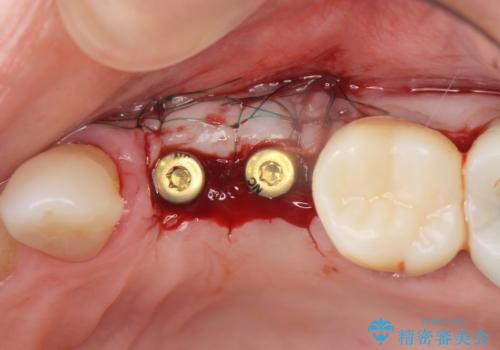

抜去後の補綴治療は長いブリッジではなくインプラント治療を希望されましたが、穿孔・破折による周囲の骨吸収をリカバリーすべく骨の造成を伴うインプラント治療を計画します。

- 97.9万円(インプラント×2・アバットメント×2・仮歯×2・ジルコニアクラウン×2・骨造成)費用は治療当時の料金となります

インプラント治療を行うにはインプラント周囲に十分な骨の幅・高さが必要です。

今回はが原因で失われてしまった骨の幅を回復することで長期的な予後を見込めるインプラント治療を行うことができました。